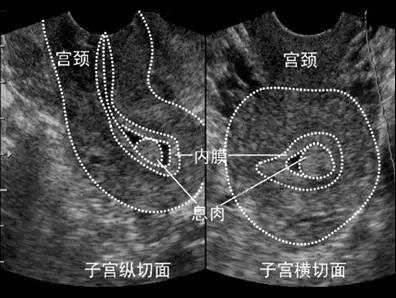

首先,进入试管婴儿(IVF)周期治疗前需行一次全面的超声检查。目的是初步测量子宫和卵巢的大小、筛查子宫畸形、附件或盆腔内病变和包块,评估双侧卵巢储备状况。必要时还需三维超声检查,进一步明确子宫及宫腔形态,以排除IVF治疗的禁忌症;

进入IVF周期后,在月经周期第2~3天,需至生殖中心行基础超声检查,通过测量双侧卵巢内窦卵泡的大小及个数,评估本周期卵巢的基础状态,以确定促排卵的方案及药物剂量。如果有优势卵泡提前出现者,根据的个体情况,制定下一步治疗方案。